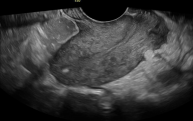

A plain abdominal radiograph demonstrated an IUCD positioned abnormally within the pelvis (Figure 1). Two-dimensional transvaginal ultrasonography re vealed a hyperechogenic focus near the uterine fun dus, raising suspicion of uterine perforation (Figure 2). Three-dimensional transvaginal imaging offered superior anatomical detail, clearly demonstrating: an empty uterine cavity, partial extrusion of the IUCD through the posterior lower uterine segment into the peritoneal cavity, and a hyperechogenic spot corres ponding to fundal trauma, likely resulting from a prior unsuccessful blind retrieval attempt (Figures 3–8). These findings confirmed uterine perforation with partial migration of the device.

Figure 2. Shows a hyperechogenic area at the fundus that indi cated the area of perforation during the blind dilatation and curet tage that she underwent before presentation to our facility.